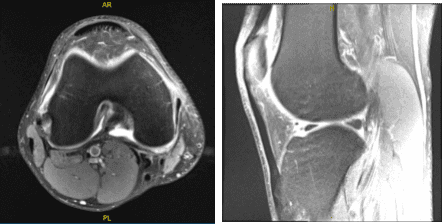

MRIs were reviewed and discussed during the visit. The results have shown complex medial meniscus tear and reactive medial collateral ligament sprain. Very small joint effusion.

MRI-3T Right Knee non-contrast